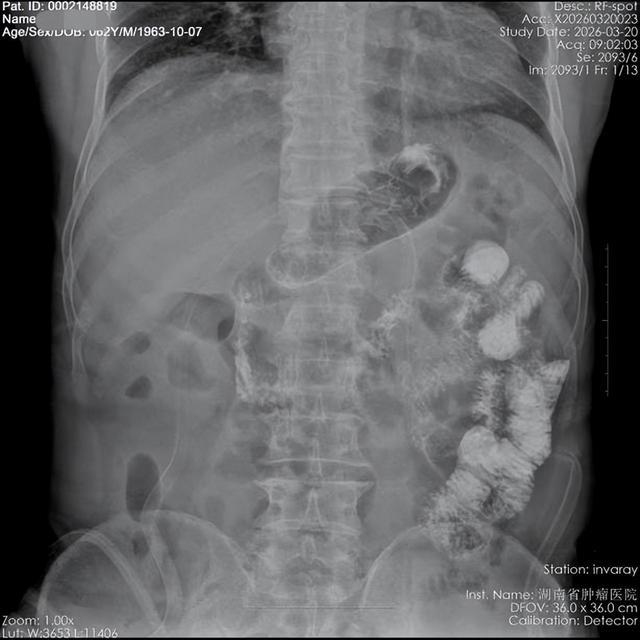

手术历时4小时顺利完成。术后造影检查显示,患者吻合口通畅,即便在头低脚高位亦未见反流现象。患者于术后第7天康复出院。

(▲头低脚高位:无胃食管反流)